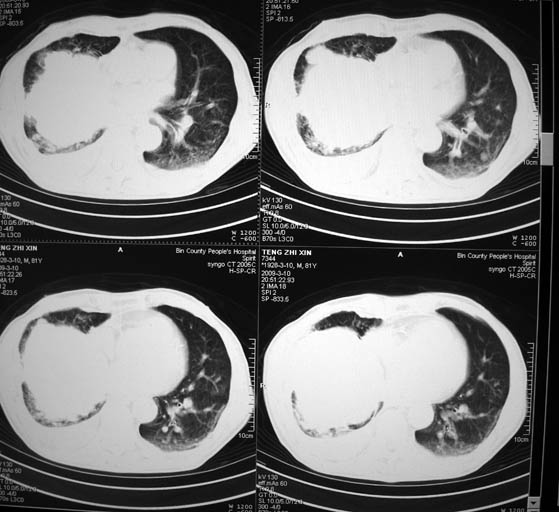

标题: CT18642:男,81岁,发热待查。

男,81岁,发热待查,右侧是占位还是膈疝?

1)考虑右肺下叶中央型肺癌并左肺转移。2)两肺上叶结核(陈旧性)。3)双侧胸腔积液。4)腹水。

很明显的排除膈疝。考虑右肺中央型肺癌,建议增强。胸腔恶性胸水。